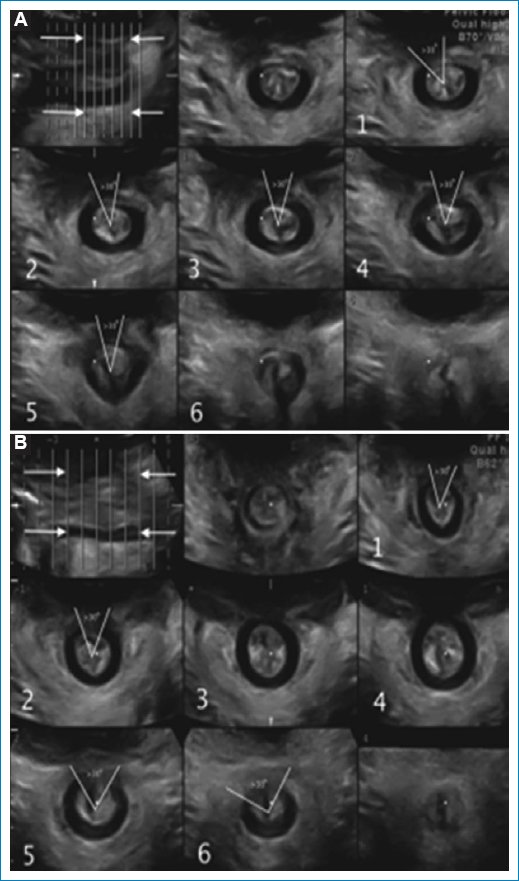

• – Evaluación del esfínter anal: para valorar el esfínter anal se deben realizar dos movimientos, a partir del plano mediosagital, un giro de 90 grados y una inclinación de la sonda hacia el canal anal, obteniendo una imagen axial del esfínter anal2. Se debe realizar su inspección en 3D y 4D con cortes tomográficos multicorte donde se pueden detectar lesiones del esfínter anal. La ecografía endoanal sigue siendo de elección, sin embargo la ecografía transperineal puede detectar lesiones, hipertrofia del esfínter anal interno en fisuras crónicas y fistula anal (Fig. 16).

Figura 16. (A) Cortes axiales donde se observa una cicatriz del esfínter anal interno. (B) Untrasonido tomográfico transperineal donde se observa una lesión del esfínter anal interno.